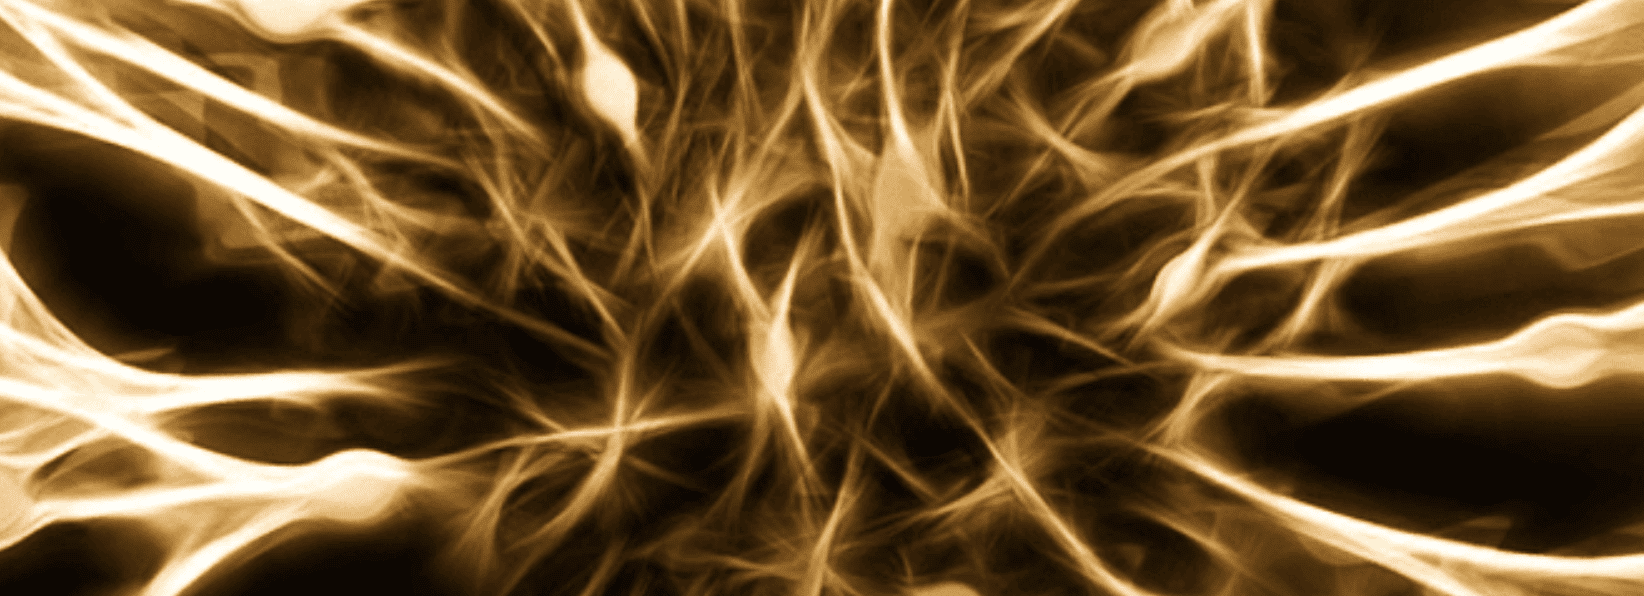

The painful symptoms in the legs caused by damages in the nerves tissues are medically known as Diabetic Neuropathy.

Diabetic Neuropathy is a common and serious complication for people who have type 2 and type 1 diabetes.

This condition develops slowly, sometimes for several years. Yet, adequate control of the disease and a healthy lifestyle can help reduce the aggravation.

All diabetic neuropathies develop gradually and progressively, making it difficult to notice any serious problems until considerable damage has been done.

When these symptoms appear, is important to bear in mind that the functioning of the digestive, urinary, circulatory system and the body’s natural healing systems, may also start to get affected.